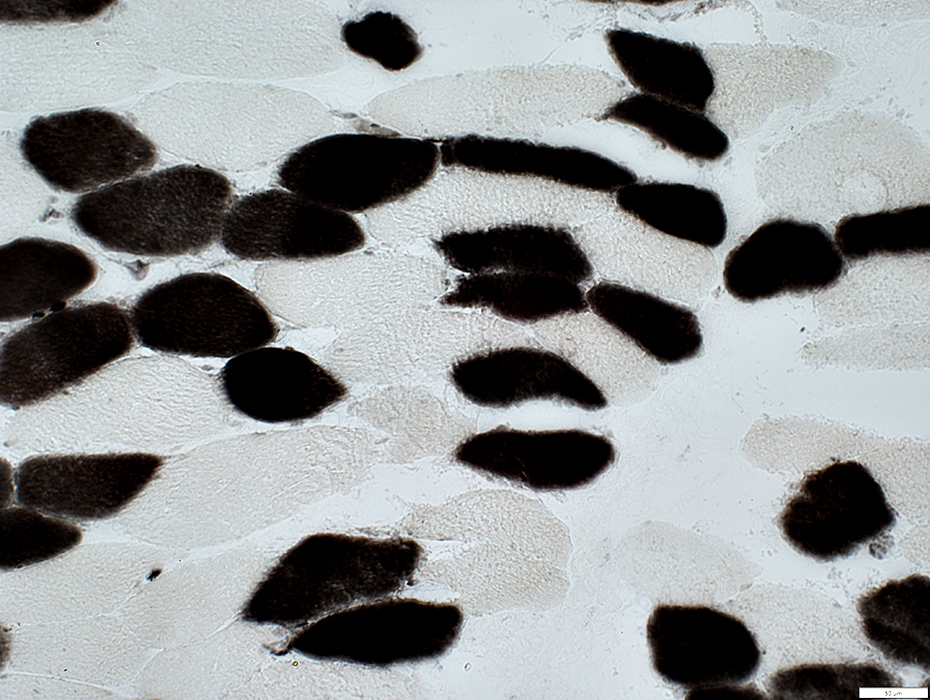

COX stain

COX negative muscle fibers

Muscle fibers with reduced staining

Mitochondria not visible